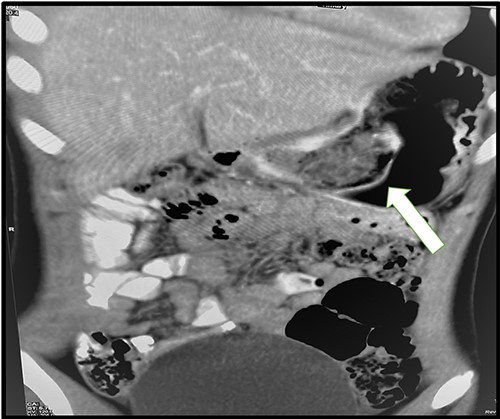

A 12-year-old girl presented to our surgical emergency department complaining of a 5-day history of severe colicky epigastric and right upper quadrant (RUQ) pain associated with vomiting, nausea and anorexia. The patient had been experiencing similar symptoms for the past month. She was otherwise healthy with no previous medical history. According to her family, she was an active child and top in her class at school. On examination, her vitals were as follows: pulse 110 bpm, blood pressure 120/70 mmHg and temperature 37°C. Abdominal examination revealed epigastric and RUQ tenderness. Laboratory tests revealed a normal complete blood count, renal function test, liver function test, C-reactive protein and coagulation profile; however, she had elevated amylase (141 U), lipase (138 U/L) and urine amylase (1776 U/L). The abdominal ultrasound was unremarkable. The patient was admitted to the surgical ward and kept fasting with intravenous fluids, an anti-spasmodic and painkillers. However, she did not improve symptomatically; her lipase increased (148 U/L), and her abdominal pain became more aggravated. A computed tomography (CT) scan of the abdomen and pelvis revealed only minimal pelvic fluid with a foreign body at the pylorus and first part of the duodenum (Fig. 1). An endoscopic attempt to extract was unsuccessful due to the size of the bezoar as well as the high possibility for respiratory tract obstruction.